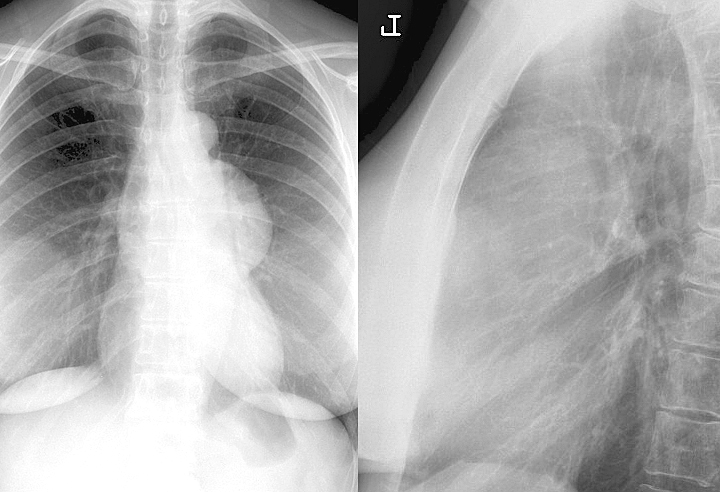

Gallery Mediastinum Thymus 006c

006c